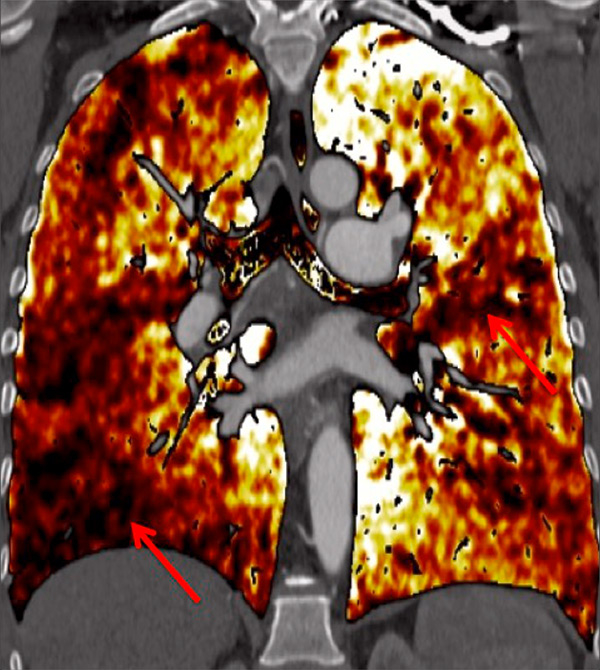

Figure 7

Portopulmonary hypertension in a 16-year-old. No abnormalities were found on morphological computed tomography (A/B), but heterogeneous perfusions were present on the perfusion map (stars, C/D).